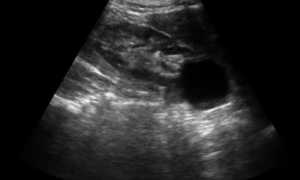

Гиперактивный мочевой пузырь является диагнозом исключения, то есть сначала врач должен исключить все возможные причины расстройств мочеиспускания такие как: воспаления мочевого пузыря, камни мочевого пузыря, рак мочевого пузыря и многое другое. Только полностью исключив эти состояния можно с уверенностью говорить о наличии ГАМП. Стандартный план обследования пациентов включает: осмотр врача, а у женщин – осмотр в гинекологическом кресле; общий анализ мочи и посев мочи на микрофлору; УЗИ почек и мочевого пузыря; урофлоуметрию с определением остаточной мочи; а при необходимости и цистоскопию с последующим уродинамическим исследованием.

• УЗИ мочевого пузыря;

• УЗИ. Позволяет оценить состояние почек, их местоположение и работоспособность.

Измерение объема остаточной мочи. Когда Вы мочитесь или происходит подтекание мочи, вероятно, что Ващ мочевой пузырь опорожняется не оплностью. Остаточный объем мочи может вызывать симптомы, идентичные симптомам гиперактивности мочевого пузыря. Чтобы измерить количество остаточной мочи после опорожнения мочевого пузыря необходимо измерить объем остаточной мочи после мочеиспускания. Это может быть выполнено с помощью катетеризации . Альтернативным методом является ультразвуковое исследовние содержимого мочевого пузыря.